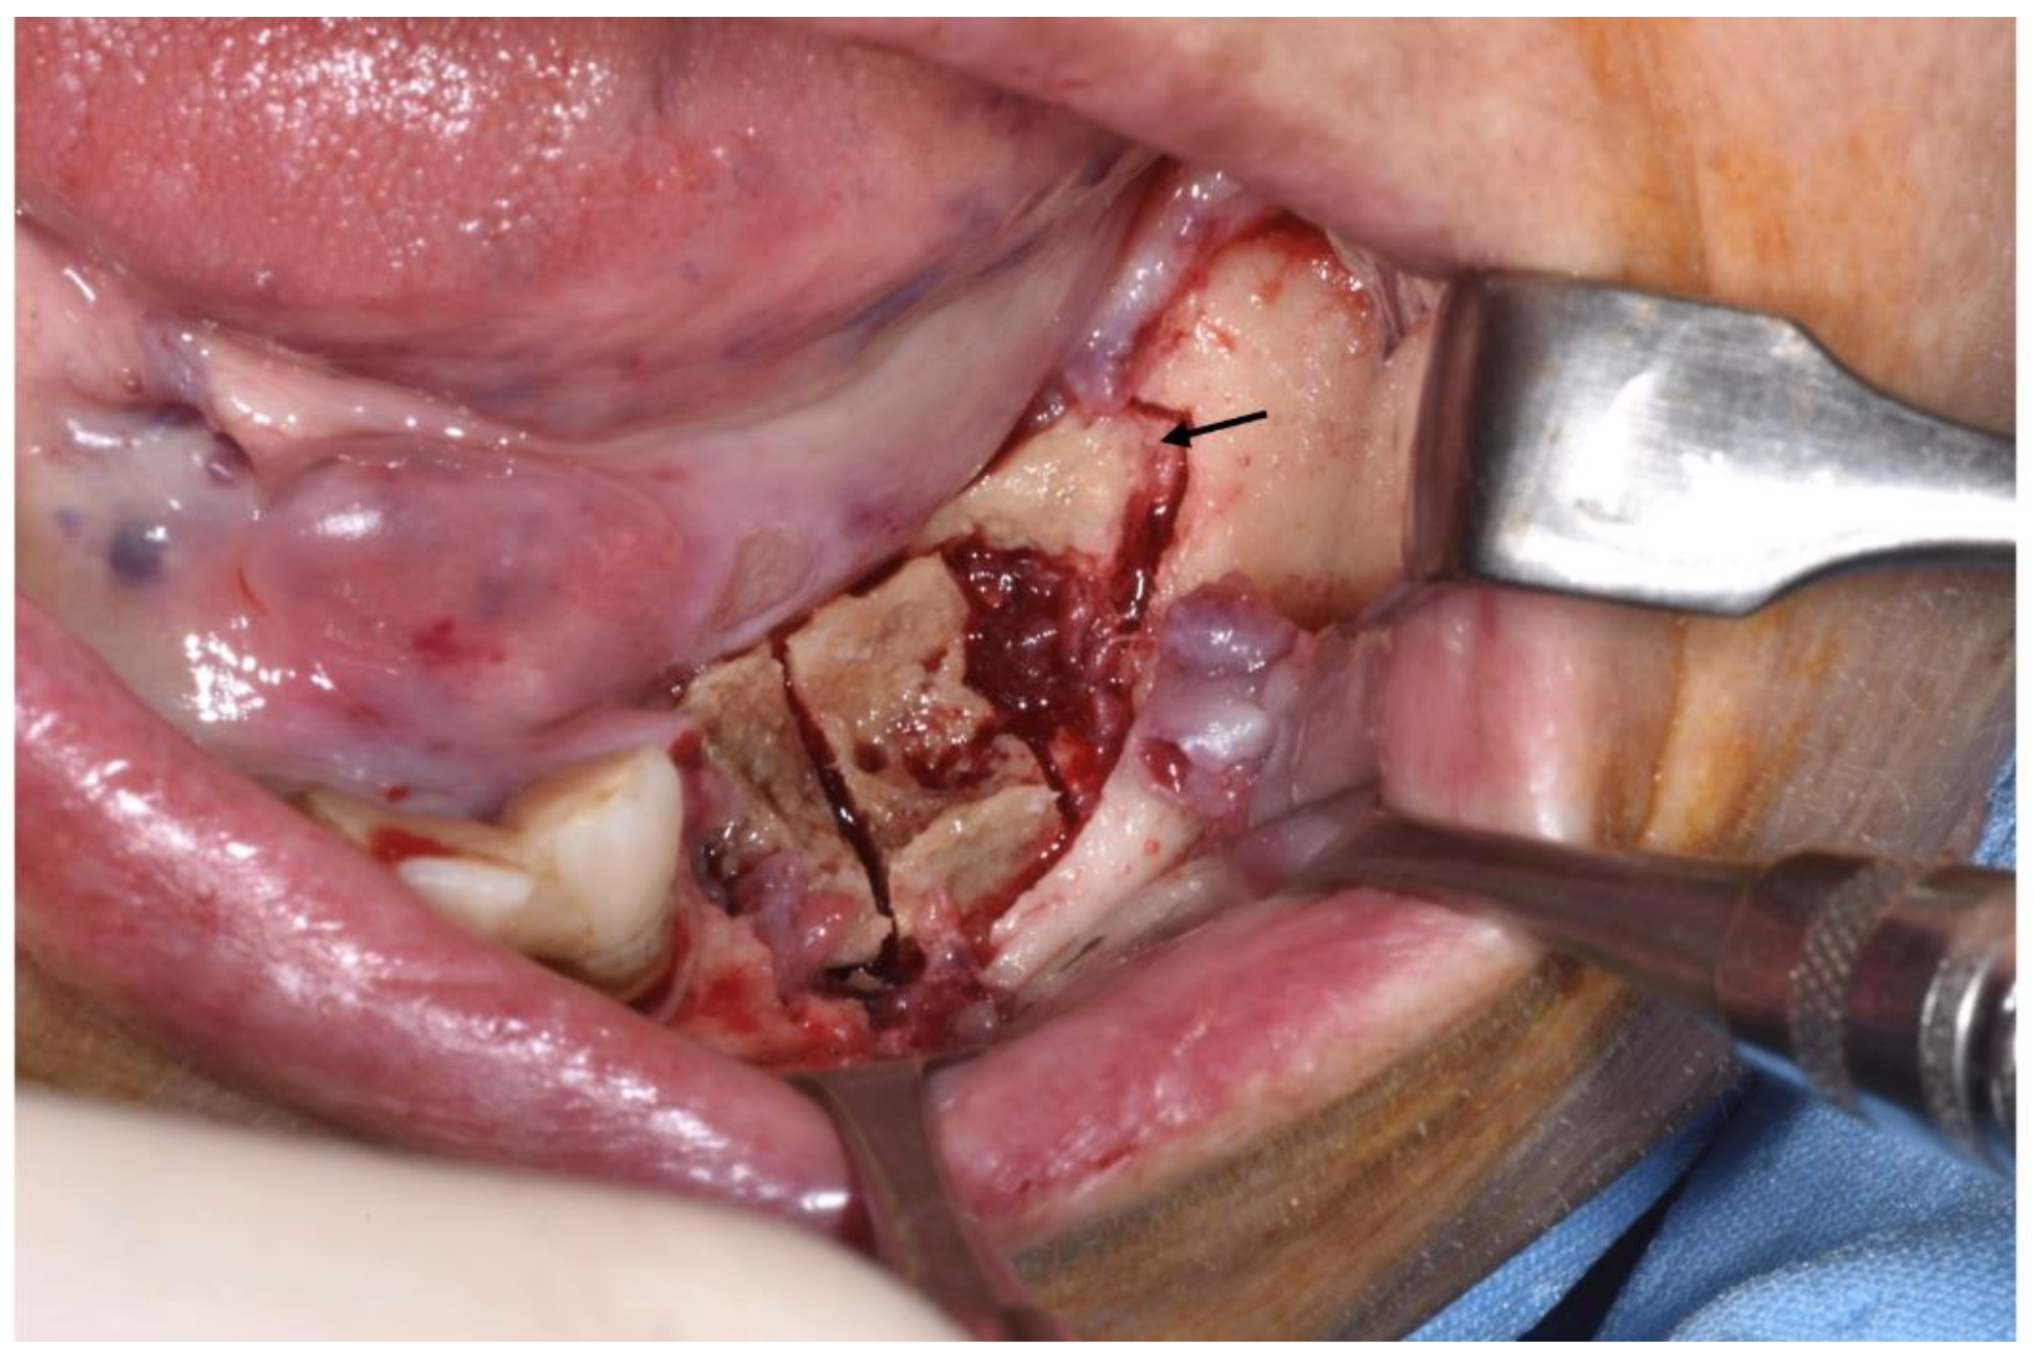

Figure 5.

Intraoperative aspect. Necrotic bone segment was observed macroscopically and cut, dividing it into three parts: a transitional zone (segment located in the mesial third of the sequestrum), totally necrotic tissue (the middle part of the segment) and healthy adjacent tissue (the distal area of the segment). The arrow schematically indicates the portion used in this case.